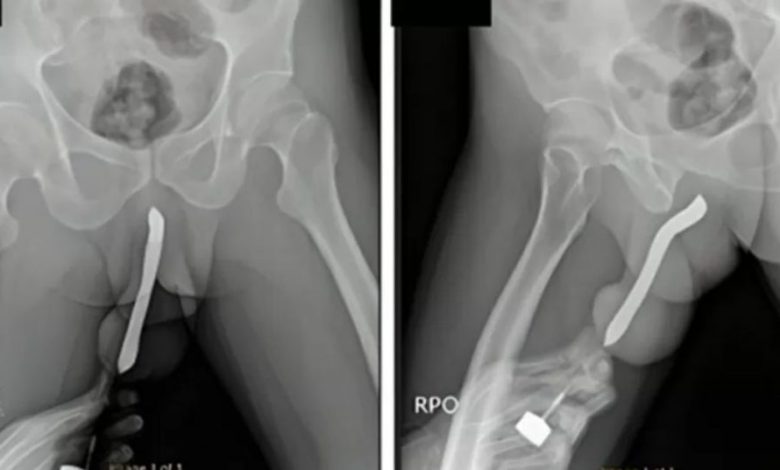

O paciente, cuja identidade não foi revelada, chegou ao pronto-socorro aproximadamente doze horas após o incidente. Ele havia inserido a escova de dentes no pênis durante uma relação sexual, resultando na quebra do objeto.

O homem teria chegado no local apresentando sintomas como dor, inchaço e hematoma. Após a comprovação do objeto em seu corpo, ele passou por uma cirurgia de remoção e conseguiu se recuperar, recebendo alta três dias depois de ter realizado todo o procedimento.